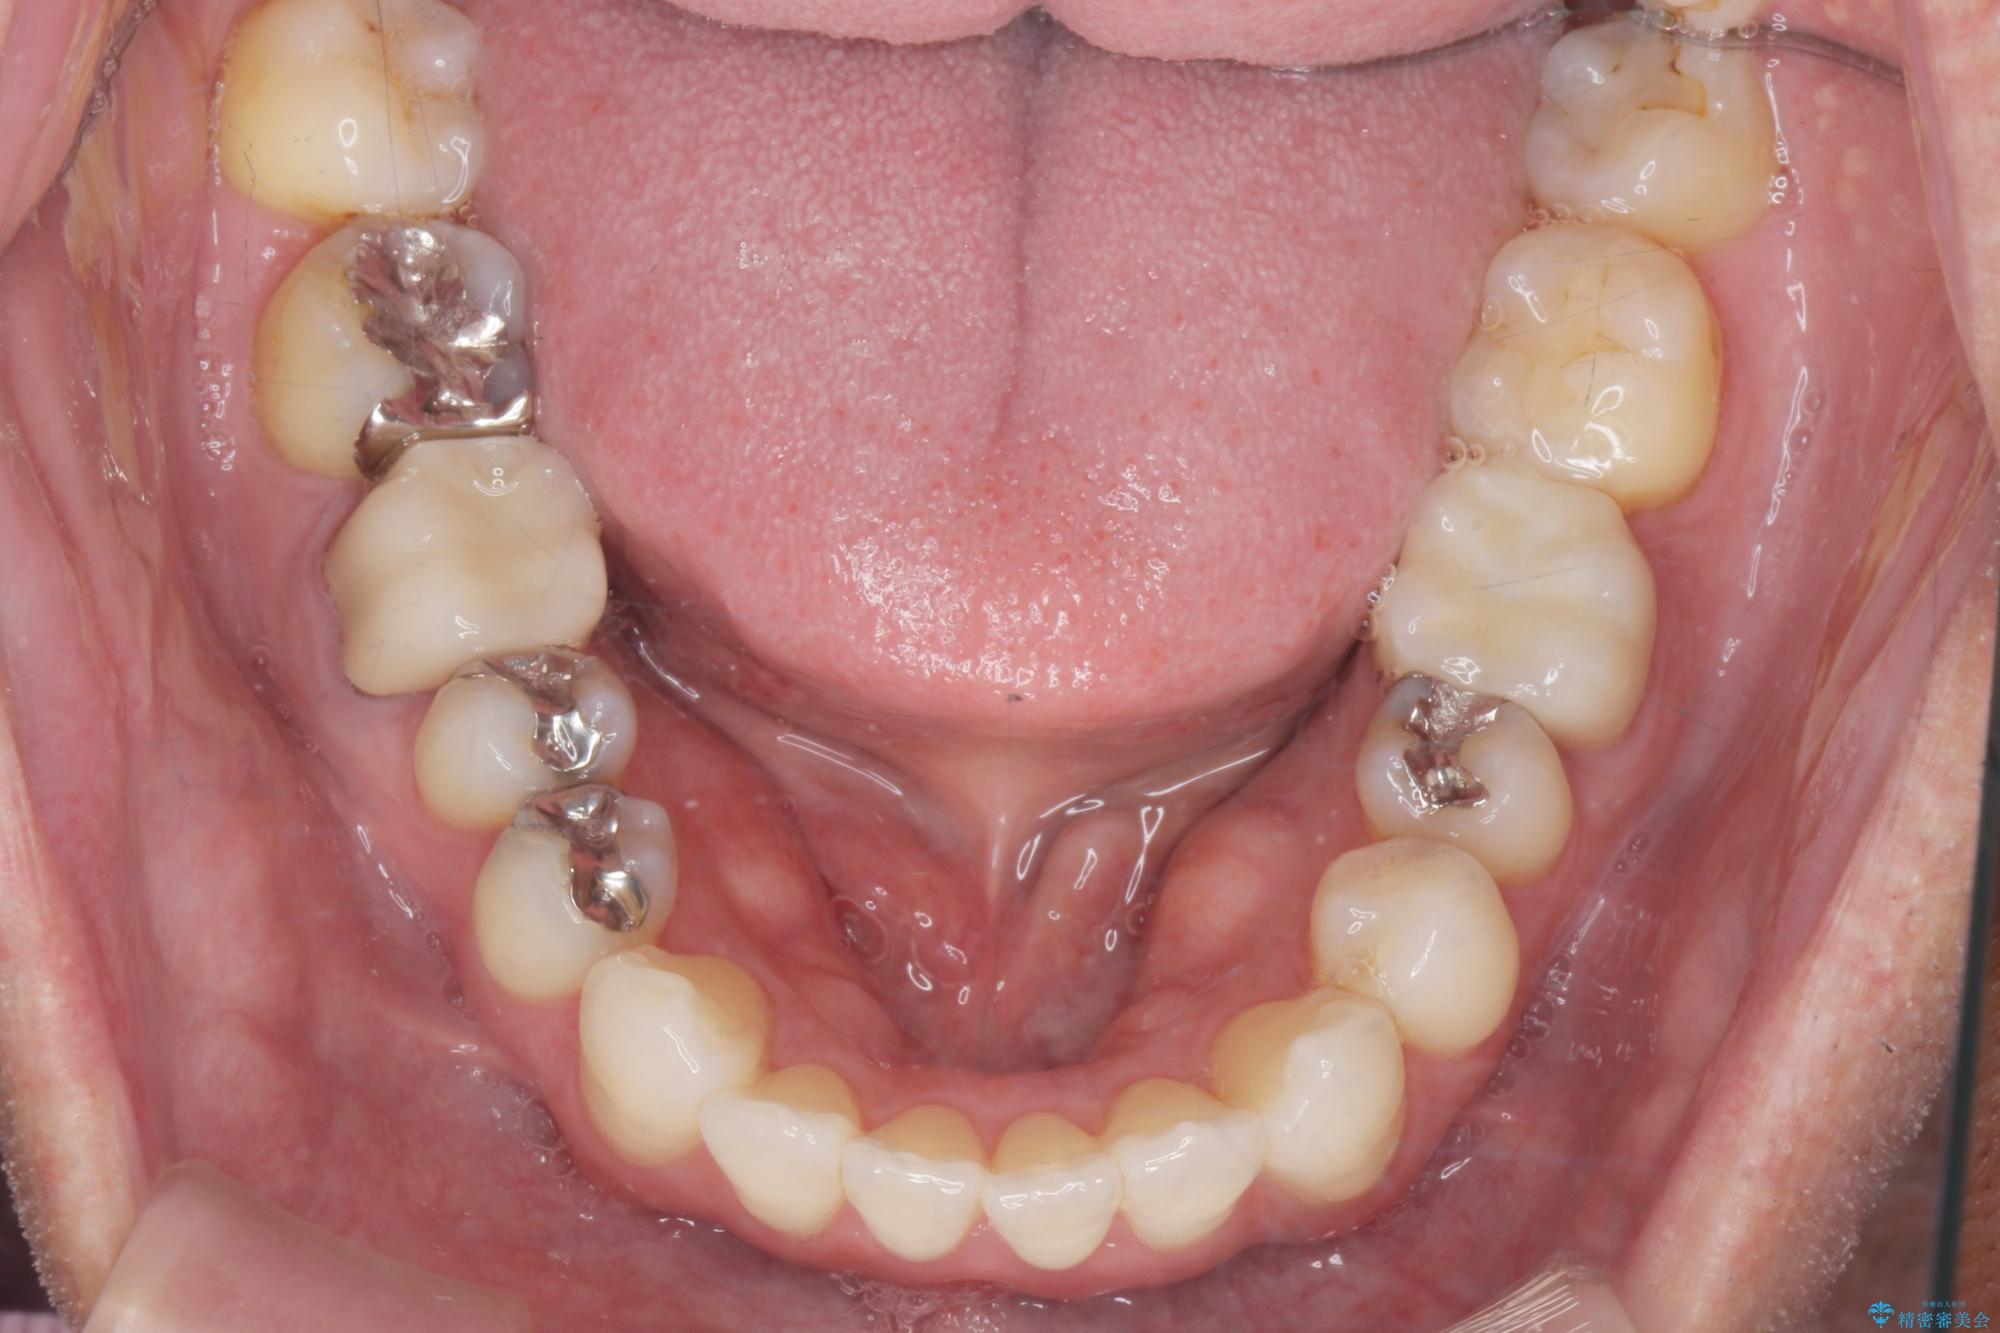

- 突き出た前歯の角度の改善と虫歯治療の改善を求めて来院されました。

虫歯を除去したのち、マウスピース矯正治療を行い、歯並びやがたつきを改善したのち、セラミックに置き換えることで審美性の向上を計画します。